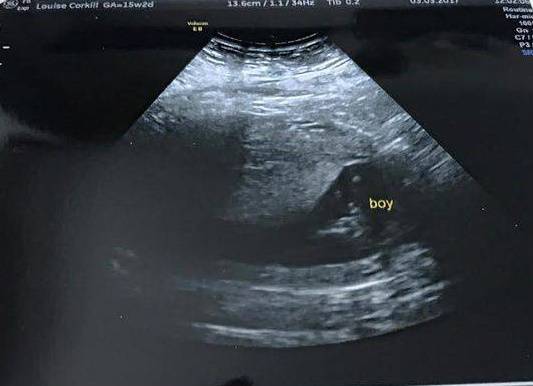

Una mamma vede una figura straordinaria durante l’ecografia del figlio – FOTO

Valentina Colmi

Una mamma inglese ha potuto scoprire una sorpresa eccezionale durante l'ecografia alla 15esima settimana: non poteva crederci.